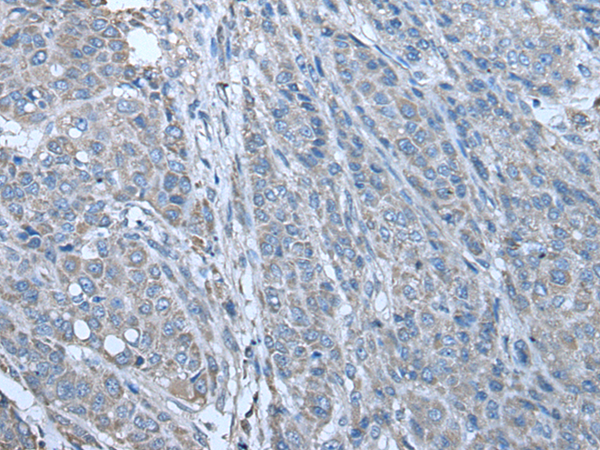

IHC positive control:

Human liver cancer and human lung cancer

IHC Recommend dilution:

25-100